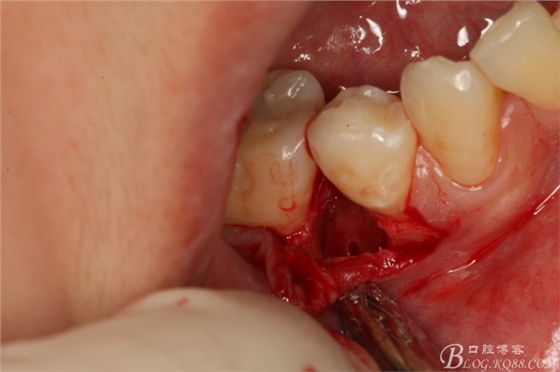

圖12.微創(chuàng)牙挺放入制備好的溝槽內(nèi)。

圖13.取出一塊牙根。給余留 牙根騰出脫位空間

圖14.緩慢在余留牙根周?chē)猛Γλ?5余留牙根

圖15.挺松的45牙根,牙根已脫位至創(chuàng)口邊緣。

圖16.取出45牙根,牙槽窩完整、不變形。